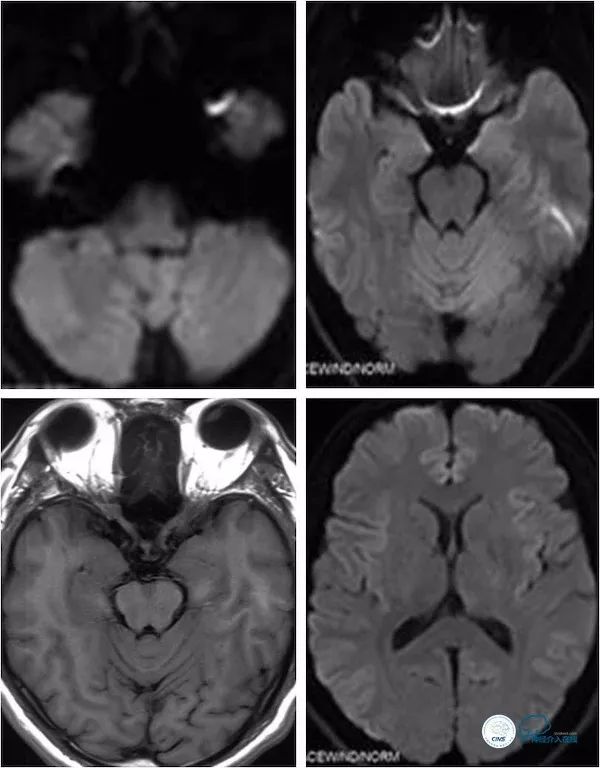

头颅MRA:右椎动脉V4段及基底动脉狭窄(图3)。

图3

头颈部CTA:左椎动脉闭塞,右椎动脉V4段狭窄,基底动脉局限性狭窄,双侧后交通动脉开放(图4)。

图4